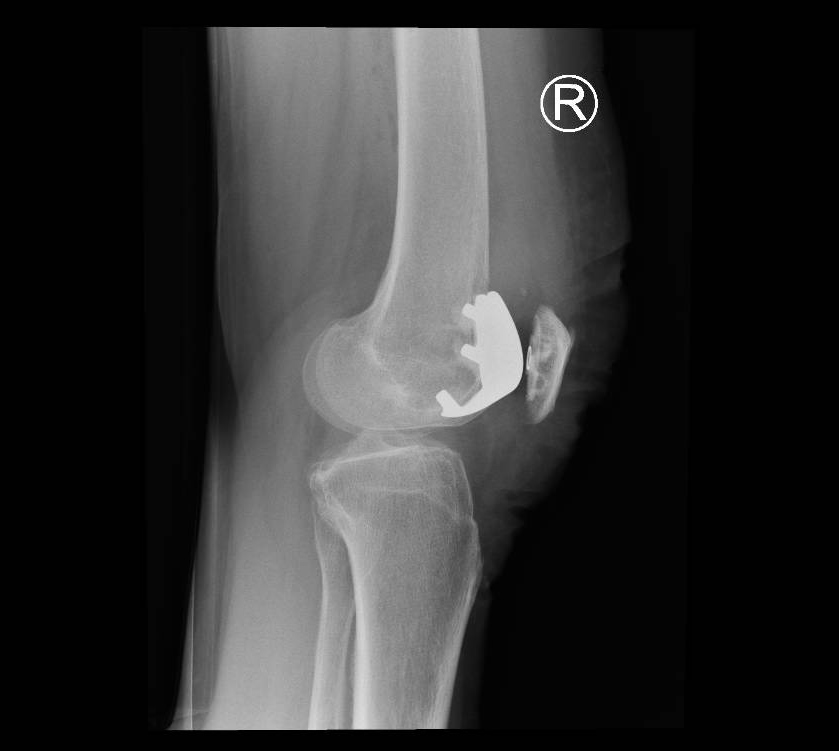

Through a minimally invasive midline incision the patellofemoral joint of the knee is replaced. This consists of a metal femoral component and a polyethelene (plastic) patella button. The unaffected medial and lateral parts of the joint are preserved along with the cruciate ligaments so the knee will feel ‘more normal’ thus providing improved functional results following surgery.

You will be admitted on the day of surgery having not eaten for the preceding 6 hours prior to the operation (nil by mouth). The anaesthetist will talk to you regarding the type of anaesthetic (spinal or general anaesthetic), it is preferable to have a spinal anaesthetic as there are fewer side effects, improved pain control and a speedier rehabilitation whilst in hospital. See FAQ section spinal or general anaesthetic.

After surgery patients generally remain inpatients for 1-3 days. Patients mobilise full weight bearing on the same day of their surgery and generally go home with a stick or crutch for 1-2 weeks. After 4-6 weeks the vast majority of patients will have seen a significant improvement in their knee function.